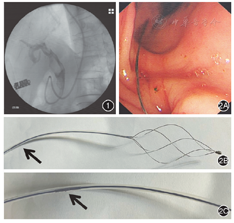

患者女,56岁,因"反复上腹痛半年,再发伴加重2周"入院。患者2周前因腹痛在当地医院就诊,查上腹部CT及磁共振胰胆管成像(magnetic resonance cholangiopancreatography,MRCP)提示胆总管巨大结石,肝内外胆管扩张,ERCP检查示胆总管巨大结石,予ERCP+经内镜乳头括约肌切开术(endoscopic sphincterotory, EST)+取出部分结石+经内镜鼻胆管引流术(endoscopic nasobiliary drainge,ENBD),为进一步取石带鼻胆管来我院。入院查体:体温36.7℃,血压95/61 mmHg(1 mmHg=0.133 kPa);皮肤巩膜无黄染,腹软,中上腹压痛,无反跳痛,余未见明显异常。入院后辅助检查:白细胞数5.3×109/L、中性粒细胞数2.6×109/L、C-反应蛋白2 mg/L;丙氨酸氨基转移酶78 U/L,门冬氨酸氨基转移酶68 U/L,γ-谷氨酰基转移酶365 U/L,碱性磷酸酶109 U/L,总胆红素21.2 μmol/L;肾功能、电解质及凝血指标等均正常。考虑诊断:困难胆总管结石ENBD术后;肝内外胆管扩张。入院后予ERCP造影见胆总管约2.0 cm×2.5 cm巨大结石(图1)。予以柱状气囊1.2~1.5 cm,压力4 ATM,扩张约2 min,用碎石网篮机械碎石后取出大量结石,再次以螺旋网篮清扫残余结石时发生网篮嵌顿断裂(图2),因断端较短,无法紧急镜内碎石,予以留置鼻胆管后行3次ESWL,冲击波冲击共计17 933次,总能量710.80 J(图3)。再次ERCP时以异物钳顺利取出网篮断端,并取净结石(图4)。